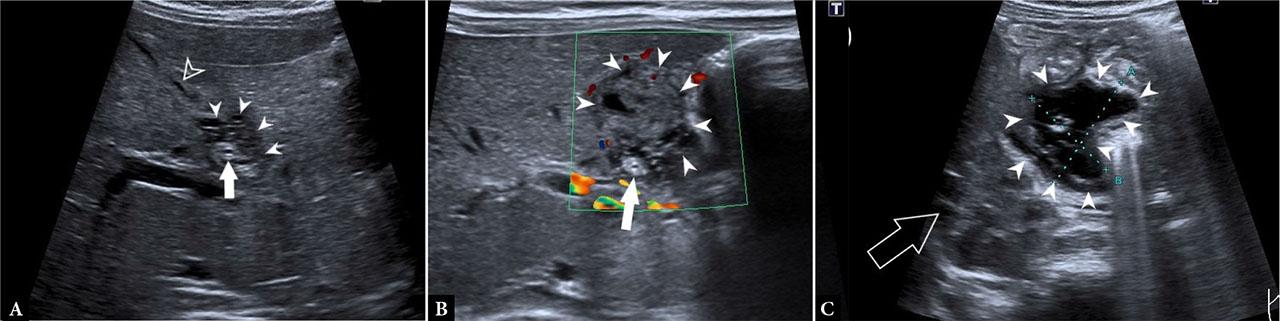

A full-term 28-day-old female infant was admitted with vomiting, diarrhea, and jaundice. The child was vitally stable and afebrile but vomited after every meal. Clinical examination showed generalized abdominal tenderness, and laboratory tests showed elevated gamma-GT (9.43 µkat/L) and elevated total and direct bilirubin (90 µmol/L and 33 µmol/L, respectively) levels. Abdominal US showed a 28 × 14 mm hypoechoic, septated formation located at the liver border within the hepatoduodenal ligament. The gallbladder was contracted, with an irregularly thickened wall and no signs of hyperemia. The choledochal duct wall was concentrically thickened and hyperechoic, with adjacent peritoneal fat showing thickening and hyperemia (Fig. 2). These findings were suspicious for gallbladder perforation. To further define the anatomical location and extent of the septated formation, contrast-enhanced abdominal MRI was performed, revealing a fluid collection extending from the hepatoduodenal ligament to the anterior pararenal space. There was no restriction of diffusion. Subsequently, HIDA scan and single-photon emission computed tomography (SPECT) were performed, demonstrating pathological bile leakage into the subhepatic collection. As the child was stable at the time and had no elevated inflammatory markers, she was treated conservatively with antibiotics. Follow-up ultrasounds were performed due to severe worsening of symptoms and elevated liver enzymes. US showed progressive changes, including increasingly hyperechoic and irregularly thickened gallbladder wall (up to 3 mm), increased concentric thickening of the common bile duct, and dilatation of the intrahepatic ducts. The fluid collection became more complex, with higher density and wall thickening. Clinical worsening, along with ultrasound findings, warranted operative intervention. Intraoperatively, a perforation was identified just below the entry point of the cystic duct into the hepatic duct. The perforated bile duct was distally stenotic and practically impassable. Cholecystectomy and Roux-en-Y hepaticojejunal anastomosis were performed.

Ultrasound findings suggestive of biliary perforation in second patient on admission: A. and B. beginning of the septated collection in the hepatoduodenal region (arrowheads), concentric thickening of the distal common biliary duct (arrow), and contracted gallbladder (empty arrowhead), C. extension of the fluid collection (arrowheads) down to the level of the right kidney (empty arrow) in the anterior pararenal space